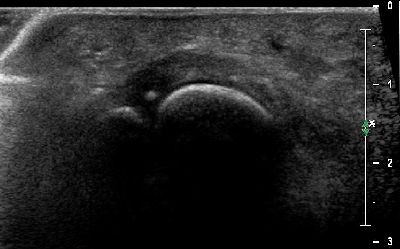

Microavulsione falange distale primo dito (img. 01) microavulsione falange distale primo dito 01